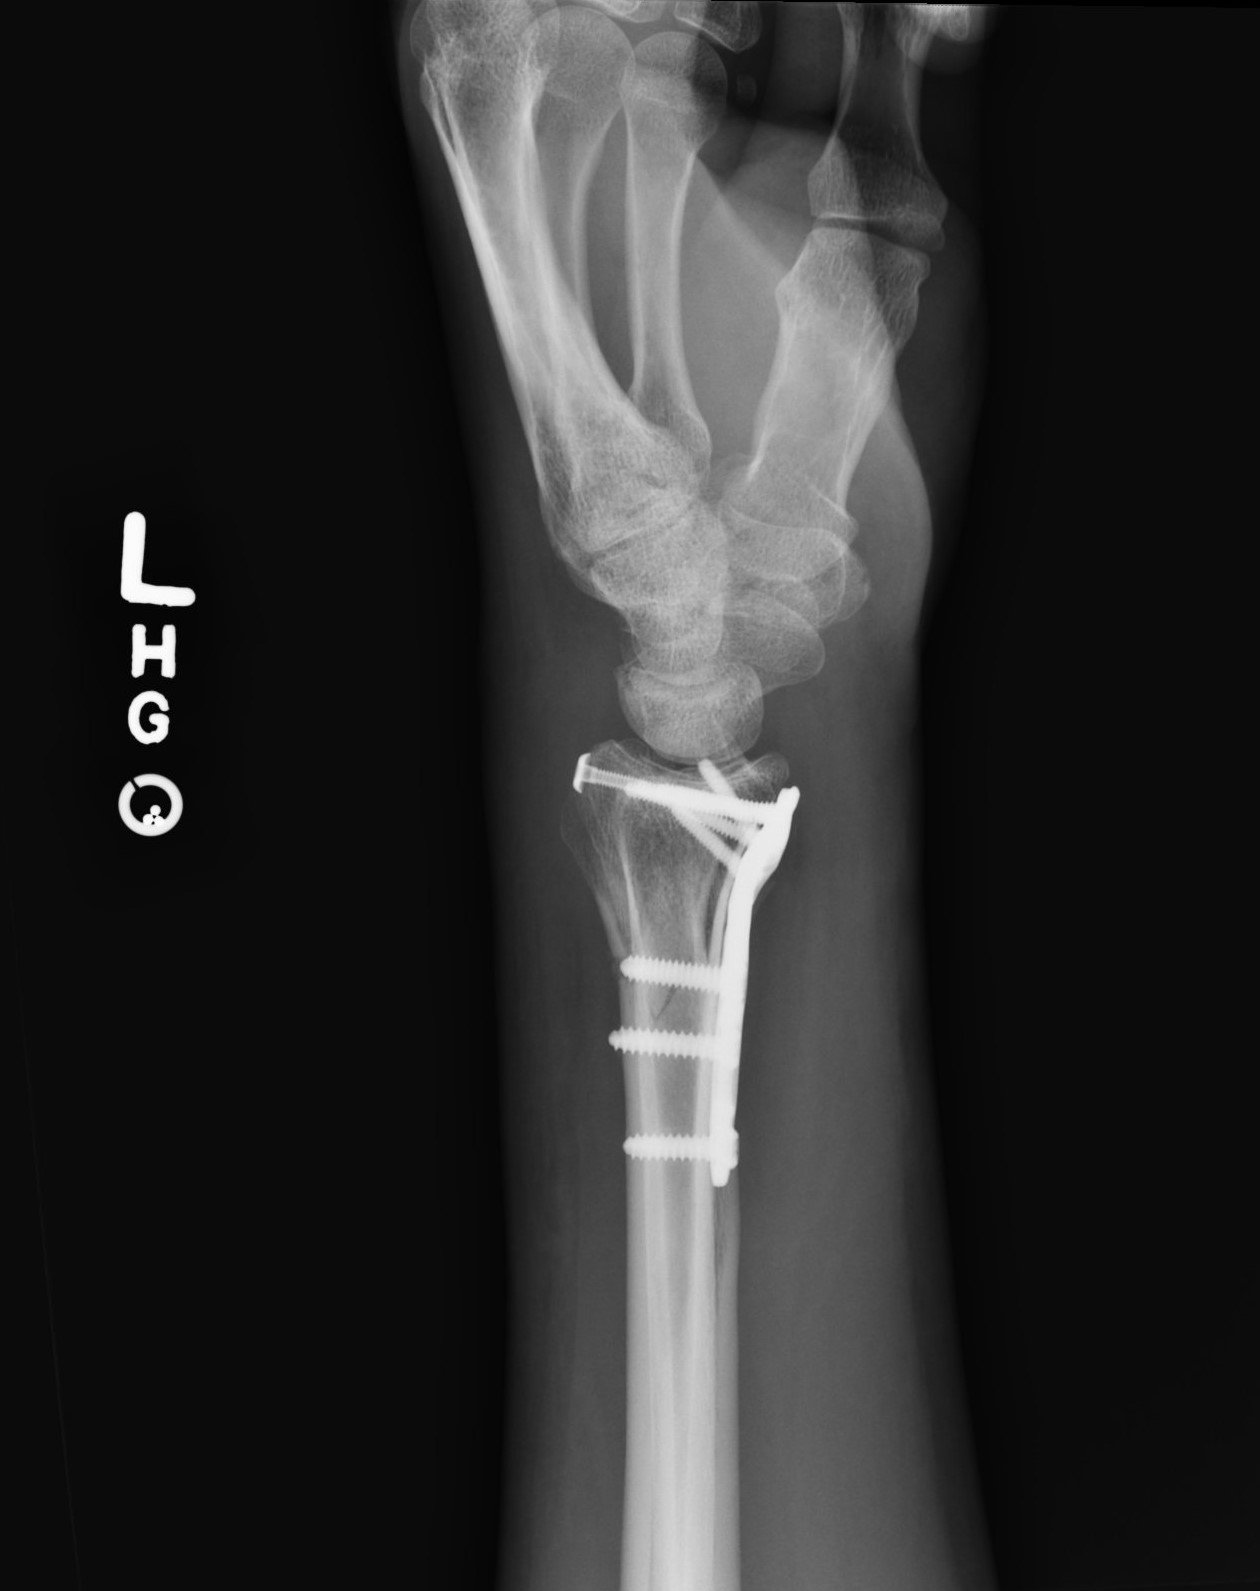

In mid-January 2021, I sustained a crushing injury to my left wrist and badly shattered it. I got very lucky considering the nature of the accident that I was not injured much more severely, and I am happy to report that surgery went well (there was worry I would need a much more invasive surgery with a much longer recovery time involving a second surgery down the road but it went about as well as possible) and a near-full recovery of wrist motion and strength is expected by a year from injury date. I of course hope to beat that timeline, and will be working my physical therapy as hard as I am allowed.